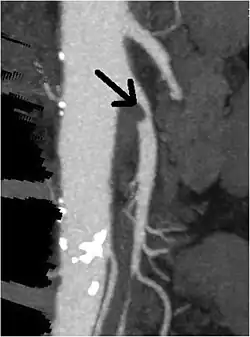

CT angiogram demonstrating stenosis of the superior mesenteric artery.

A computed tomography angiogram showing stenosis of the superior mesenteric artery (arrow).

Abdominal angina is diagnosed by identifying stenosis with imaging.[10] Since the symptoms of abdominal angina overlap with various other disorders, other causes of symptoms are ruled out as a part of the diagnostic process. Gastric ulcers, abdominal aortic aneurysms, and gastrointestinal cancers can have similar symptoms and can be ruled out by esophagogastroduodenoscopy, CT scans, or MR angiogram. Other differential diagnoses include GERD, dietary or food sensitivities, constipation, pancreatitis, abdominal abscess, appendicitis, irritable bowel syndrome, gastroenteritis, hepatitis, and inflammation of the gastrointestinal system.[11] Duplex ultrasound, MR angiography, angiography, and computed tomography angiography can be used to help confirm the diagnosis of abdominal angina.[3] Duplex ultrasound may be used to screen for abdominal angina but is not ideal for visualizing stenosis. Angiography, MR angiography, or CT angiography can be used to further visualize the celiac and mesenteric arteries.[12]